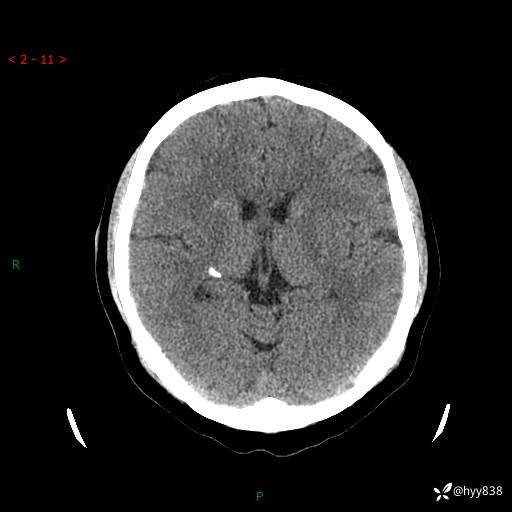

病例年轻小伙,早早的就切除了右侧肾脏,他怎么了---结果公布~

患者性别:男

患者年龄:28岁

简要病史:右肾肿瘤术后,常规复查

辅助检查:CT

临床诊断:右肾肿瘤术后

腹部CT+颅脑CT平扫